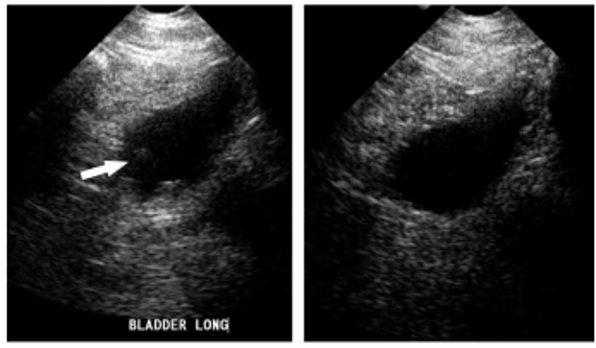

The artifact shown is reverberation caused by back and forth reflection of the ultrasound beam between 2 closely spaced interfaces. These reverberation echoes appear as multiple equally spaced lines, which decrease in intensity with increasing depth. This artifact is often caused by highly reflective interfaces, e.g., metallic objects or calcification in tissues.

reverberation artifact:

multiple equidistance echoes